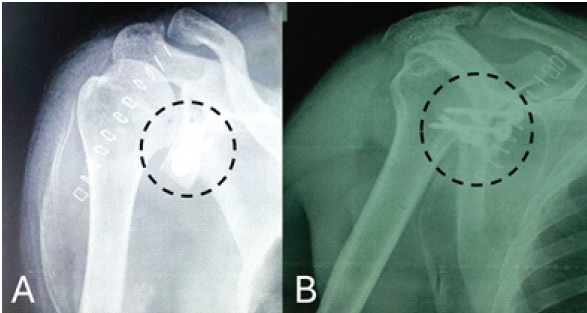

Stability and range of motion were assessed intra-operatively. Thorough wash was given, and the incision was closed in layers. The patient received post-operative antibiotics and analgesics. Physiotherapy was started on post-operative day one as per the pain tolerance, and a plain radiograph was obtained (Fig. 5).

Figure 5: Immediate post-surgery plain radiograph, (a) Humerus in anteroposterior view, (b). Humerus in lateral view, both images showing reconstructed glenoid with screws. (marked with a dotted black circle).